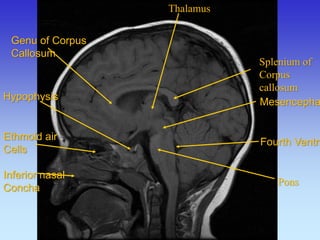

Thalamus

Splenium of Corpus callosum

Pons

Ethmoid air Cells Inferior nasal Concha

Mesencephalon

Fourth Ventricle

Genu of Corpus

Callosum

Hypophysis